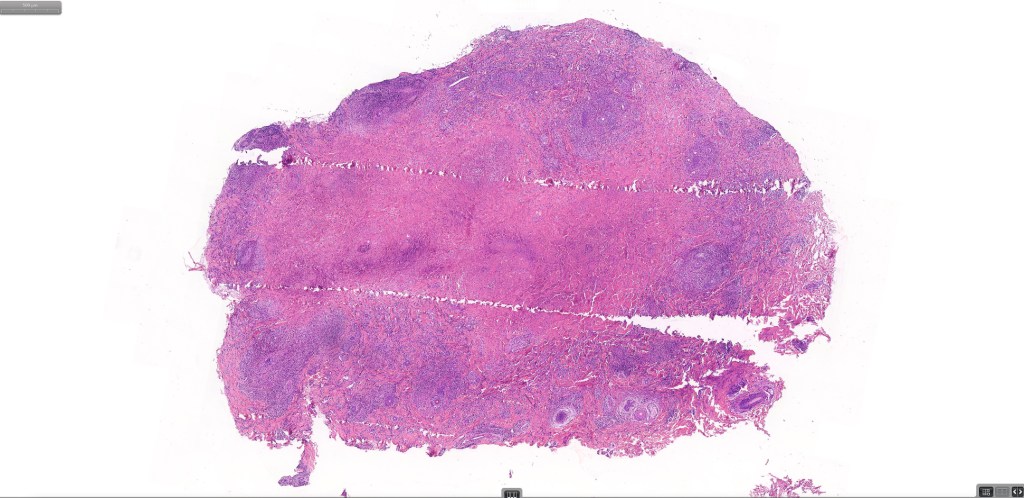

Histological features

•Subdivided into 5 major & several rarer variants

•Type A: 75-80%, wedge shaped infiltrate with base uppermost, large, anaplastic cells with abundant cytoplasm and vesicular nuclei containing prominent nucleoli, can resemble Reed-Sternberg cells, conspicuous mitoses & background infiltrate of lymphocytes, plasma cells, histiocytes, neutrophils & eosinophils

•Type C: 7-10% nodular infiltrate similar to primary cutaneous anaplastic large cell lymphoma